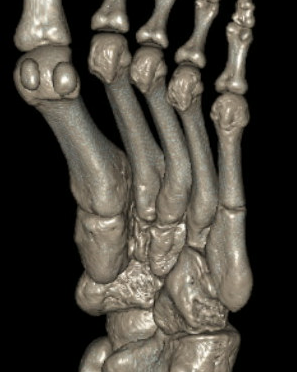

Base of 5th - Zone 1 / 2 / 3

Classification

| Zone 1 | Zone 2 | Zone 3 |

Tuberosity avulsion fractures

Metaphyseal-diaphyseal junction Involves the 4th / 5th MT articulation |

Distal to the 4th / 5th MT articulation Proximal diaphysis |

| Incidence: 93% | 4% | 3% |